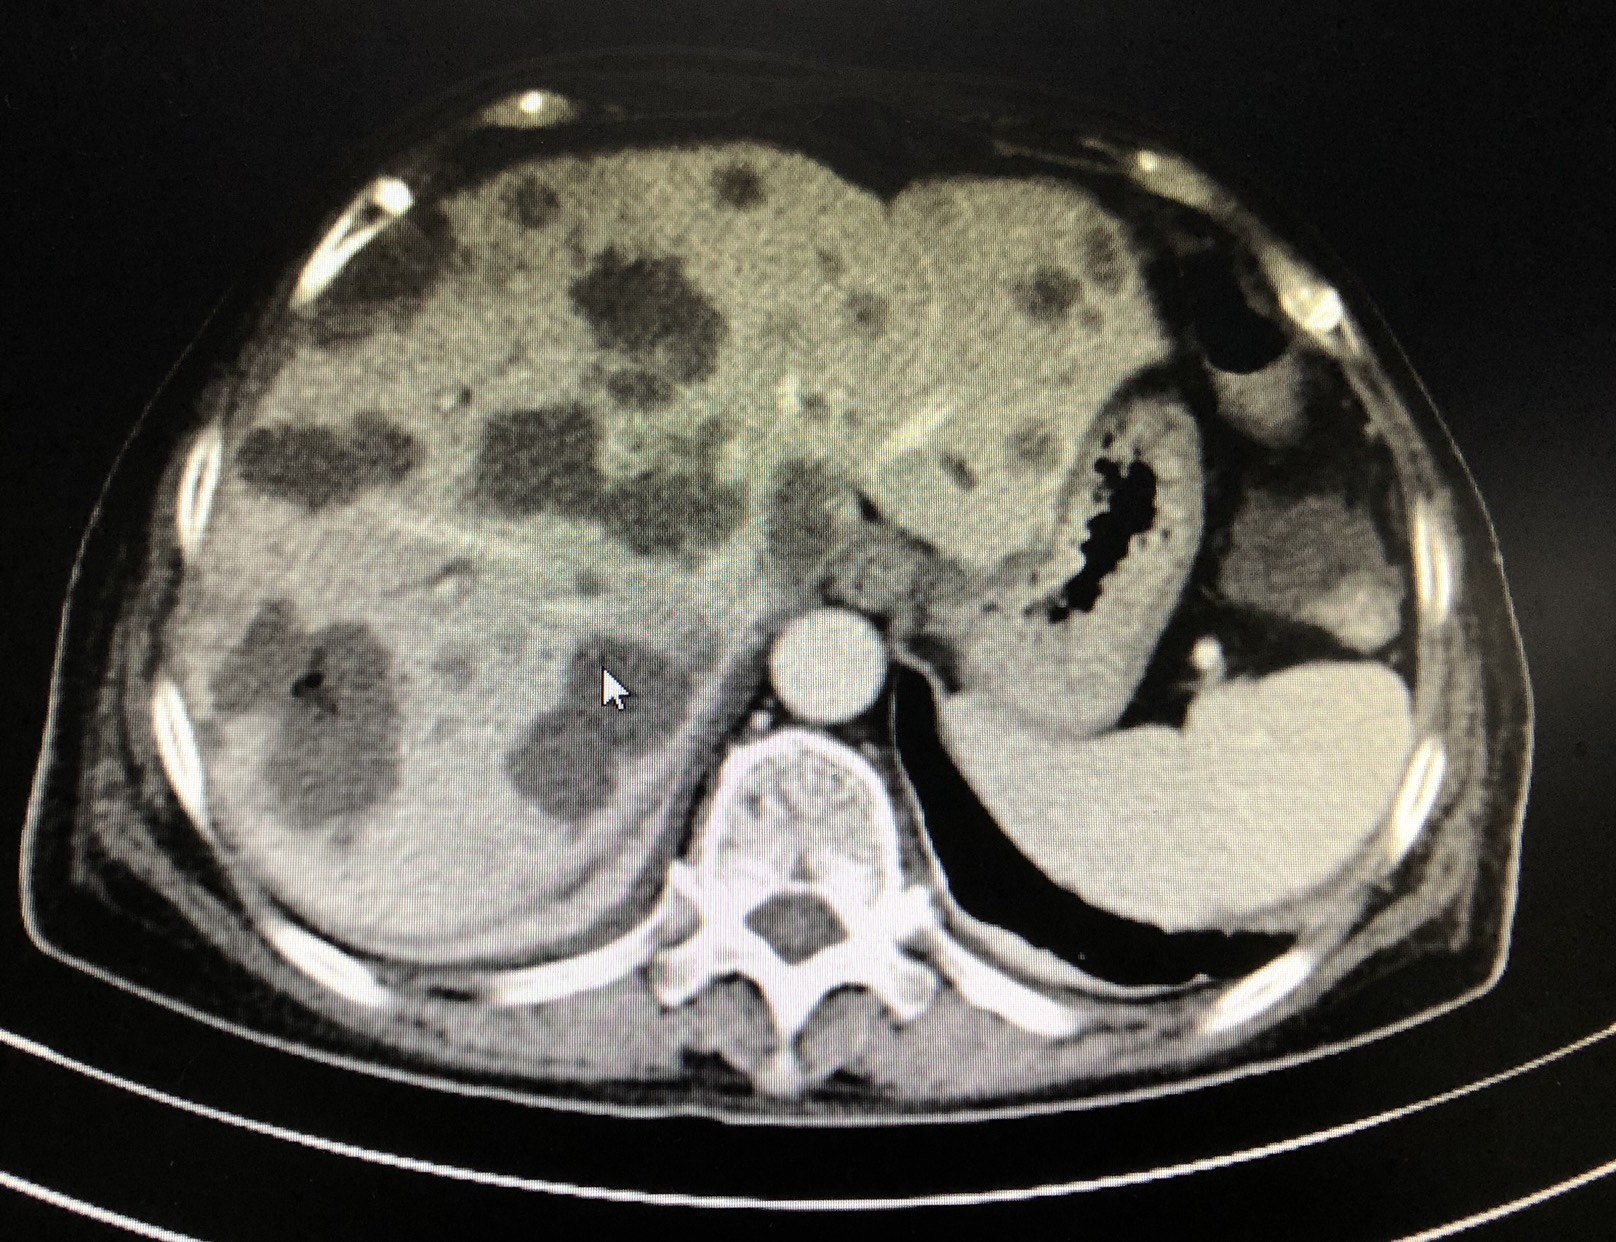

肝内典型转移瘤,考虑来源胃肠道,等进一步检查结果 - 抖音

肝脏影像系列六肝内多发转移瘤